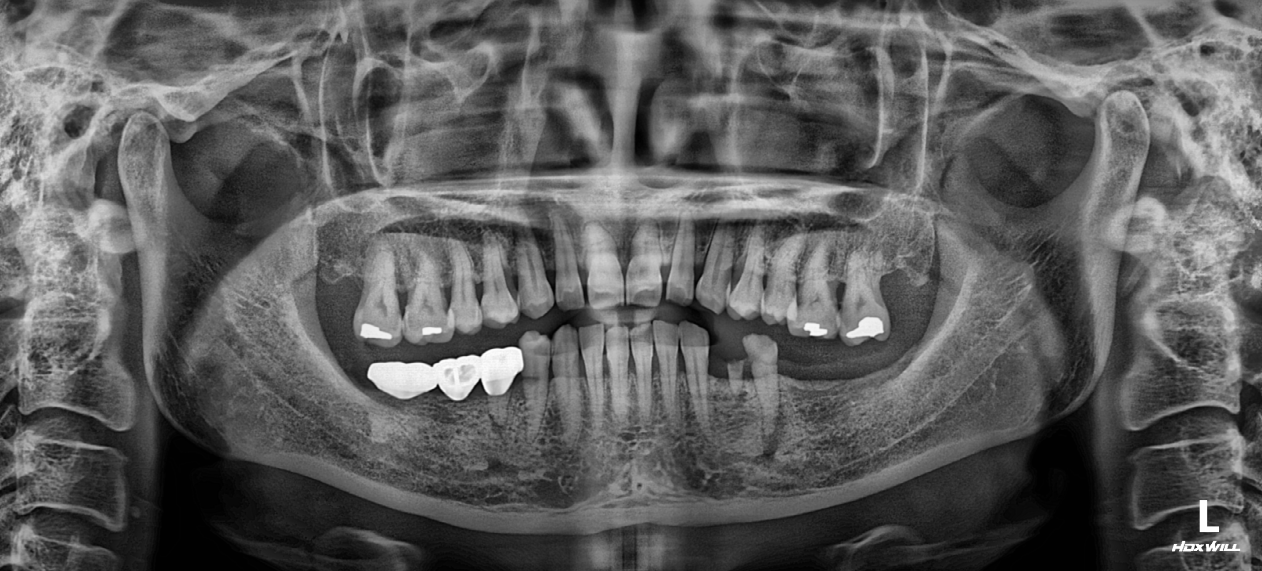

OPG - BEFORE